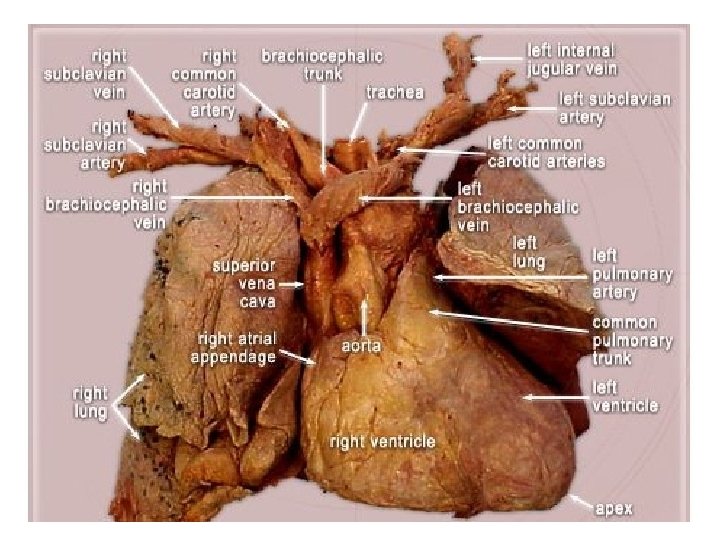

Right Brachiocephalic vein Superior vena cava Right atrium. Inferior vena cava. ØAortic knuckle, or knob (aortic arch) ØPulmonary trunk, ØLeft auricle, ØLeft ventricle.

Posteroanterior radiograph (Mediastinum) ØThe left border of mediastinum consists of: ØAortic knuckle, or knob (aortic arch), ØPulmonary trunk, ØLeft auricle, ØLeft ventricle.